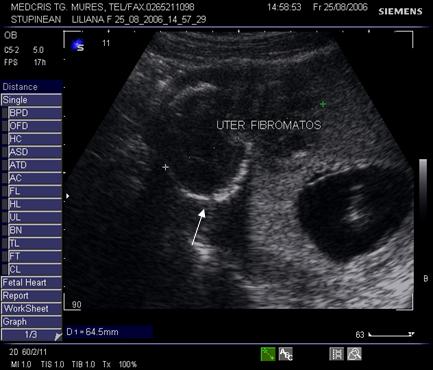

9.Sarcina si fibromul uterin

Cea mai comuna tumora uterina - leiomiomul - poate fi detectata si masurata inca de la inceputul sarcinii. Fibromul poate complica sarcina in functie de marime si pozitie. Nodulul subseros pediculat foarte rar se poate complica, in schimb nodulul submucos sau intramural creste riscul de avort spontan sau nastere prematura, dar peste 75% din aceste paciente duc sarcina la termen. Cea mai frecventa complicatie a fibromului in sarcina este necroza aseptica (25%) de obicei moderata, ea poate aparea si in lauzie. Cresterea fibromului in sarcina a fost notata in circa 22% dintre fibroame.[12]

Fibromul apare de obicei hipoecogen in uterul gravid, trebuind masurat si observat pe parcursul sarcinii.

Fig. nr. 92. Nodul fibromatos intramural hipoecogen,

alaturi de sarcina de 12 saptamani